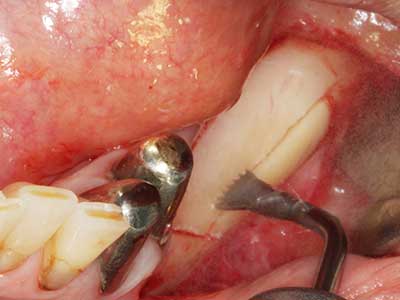

Indikation: Nervnahe Präparation

Wie bereits erwähnt lassen sich auch im Bereich der chirurgischen Zahnerhaltung Indikationsgebiete für die Piezochirurgie finden. Durch die Verwendung von speziellen Arbeitsspitzen wird die Darstellung der Wurzelspitze erleichtert, und gerade im unteren Prämolaren- und oberen Seitenzahnbereich lassen sich Nerven und Kieferhöhlenschleimhäute einfacher schützen. Bei undichtem apikalen Abschluss präparieren abgewinkelte Diamantspitzen zielgenau die Resektionskavität für das retrograde Wurzelfüllmaterial. Die Spitzen können durch die Ultraschalltechnik sehr grazil gestaltet sein, was Übersicht und Größe der Zugangskavität verbessert. So gehört in dieser Indikation die Anwendung der Ultraschallchirurgie zu den Standardverfahren der Wurzelspitzensresektion (Del Fabbro, Tsesis et al. 2010, Scarano, Artese et al. 2012).

Sollen chirurgische Eingriffe mit unmittelbarer Knochenbeziehung an empfindlichen Strukturen wie Blutgefäßen oder Nerven erfolgen, so bergen rotierende Instrumente ein erhebliches Potential an iatrogener Schädigung. Gerade bei Nervdarstellungen nach iatrogener Schädigung, oder aber im Zuge einer Nervlateralisation für resektive und rekonstruktive Eingriffe oder Implantatinsertionen können piezoelektronische Geräte hilfreich sein Knochendeckel zu präparieren und nervnahe Hartgewebsanteile zu entfernen (Abb. 17-20). Ein leichter Kontakt des Nervstrangs zur Piezospitze bleibt dabei in der Regel folgenlos – allerdings kann eine unvorsichtige Vorgehensweise mit sägeartigen Bewegungen bzw. Ansätzen bei noch vorhandener knöcherner Unterlage durchaus temporäre oder aber auch permanente Nervschädigungen verursachen. Das Risiko einer solchen Schädigung wird jedoch als wesentliche geringer eingeschätzt als unter Anwendung von Säge- oder Fräsinstrumenten (Pereira, Gealh et al. 2014).